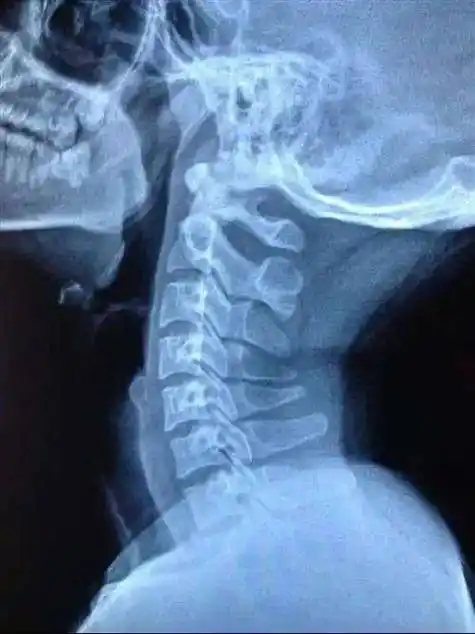

广州白领坐过山车扭了脖子,专家:颈椎病人群慎玩,严重可致瘫

颈椎就是脖子里的骨头,在身体的最上面,它是身体最灵活的关节,也因为

颈椎曲度变直怎么办颈椎曲度变直怎样治疗好